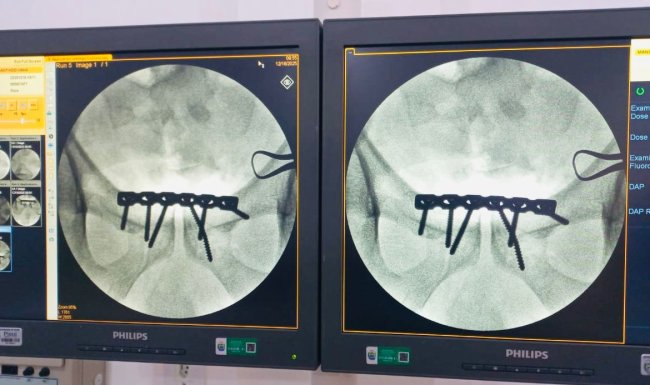

O Hospital Regional Chagas Rodrigues (HRCR), em Piripiri, realizou, pela primeira vez, o tratamento cirúrgico de fratura do anel pélvico — popularmente conhecida como fratura da bacia, representando um marco histórico para a unidade e um avanço importante na ampliação dos serviços ortopédicos oferecidos à população.

A fratura pélvica ocorre nos ossos do quadril, sacro e cóccix, que juntos formam o anel pélvico. Em casos mais graves, como quando há ruptura do anel, a fratura envolve pelo menos dois pontos ósseos, resultando em maior instabilidade e complexidade no tratamento.

O paciente, do sexo masculino, foi vítima de trauma automobilístico, apresentando fratura do anel pélvico do tipo “livro aberto”, considerada um trauma grave. Até então, casos como esse exigiam a transferência para unidades de referência em Teresina. Nesta ocasião, todo o tratamento cirúrgico foi realizado no próprio HRCR, com suporte completo de anestesia, enfermagem, materiais adequados e segurança assistencial.